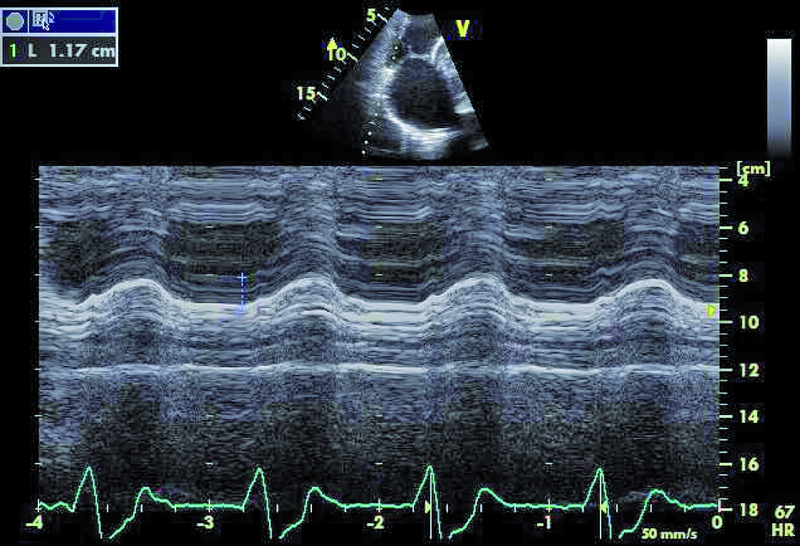

Mężczyzna, lat 35. Jakie patologie można rozpoznać na rycinach?

6. Upośledzona funkcja kurczliwa prawej komory (ryc. 4).